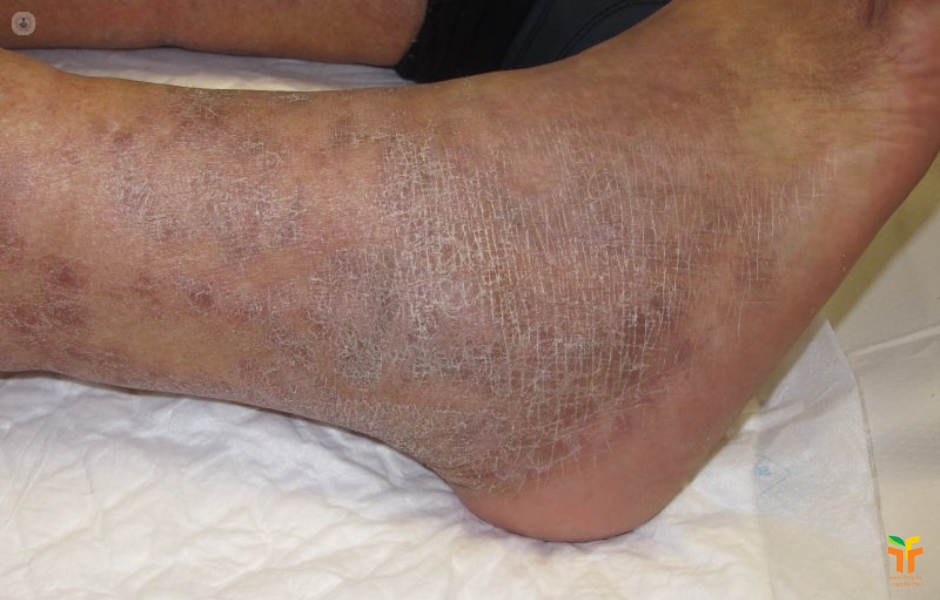

Viêm da ứ trệ là thể viêm da thường gặp ở cẳng chân, phát sinh do phù mạn tính và tình trạng ứ trệ tĩnh mạch kéo dài. Theo MSD, các triệu chứng thường gặp là ngứa, đóng vảy và tăng sắc tố; nếu không điều trị tốt, loét là một biến chứng quan trọng. Đây là một dạng viêm da rất đặc biệt vì vấn đề gốc không nằm ở mỹ phẩm hay dị ứng, mà nằm ở tuần hoàn và tình trạng sưng nề của chi dưới.

Ở giai đoạn mạn, MSD cho biết da có thể trở nên dày hơn và sẫm màu hơn. Những thay đổi da này không chỉ ảnh hưởng thẩm mỹ mà còn báo hiệu nguy cơ loét do ứ trệ tĩnh mạch. Nếu chỉ chăm chăm bôi thuốc ngoài da mà bỏ qua phù chân, suy tĩnh mạch hay các nguyên nhân gây sưng kéo dài, bệnh thường không cải thiện bền vững.

Điều trị viêm da ứ trệ vì thế phải hướng vào nguyên nhân gây phù. MSD nêu khá rõ các biện pháp chính gồm nâng cao chân, băng ép, điều trị suy tĩnh mạch mạn nếu có, và xử lý các biến chứng như loét, nhiễm trùng thứ phát hoặc viêm da tiếp xúc dị ứng kèm theo. Với vùng da chưa trợt, corticosteroid bôi tại chỗ có hiệu lực trung bình có thể giúp giảm viêm; với tổn thương rỉ dịch hoặc loét, chăm sóc vết thương đúng cách là rất quan trọng.